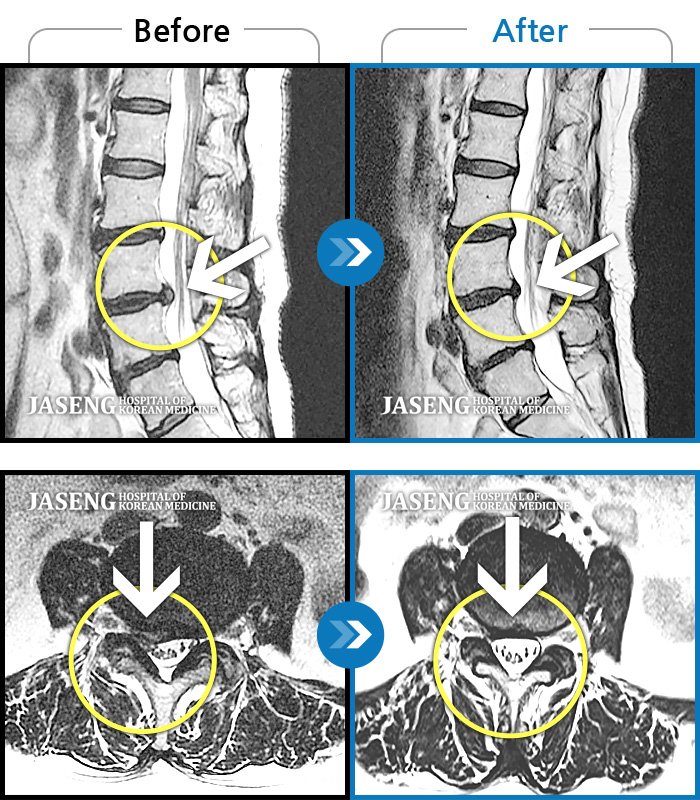

Before

After

환자에게 사전 동의를 받아 동일 조건에서 촬영되었습니다.

개인에 따라 치료 후 부작용이 발생할 수 있으니 의료진과 상담 후 치료를 진행하시기 바랍니다.

허리 양측 골반 통증, 좌측 하지 통증과 비증 동반, 기립 시 종아리 당기는 증상

허리 우측 골반 통증, 우측 다리 저리고 엄지발가락 마비 증상